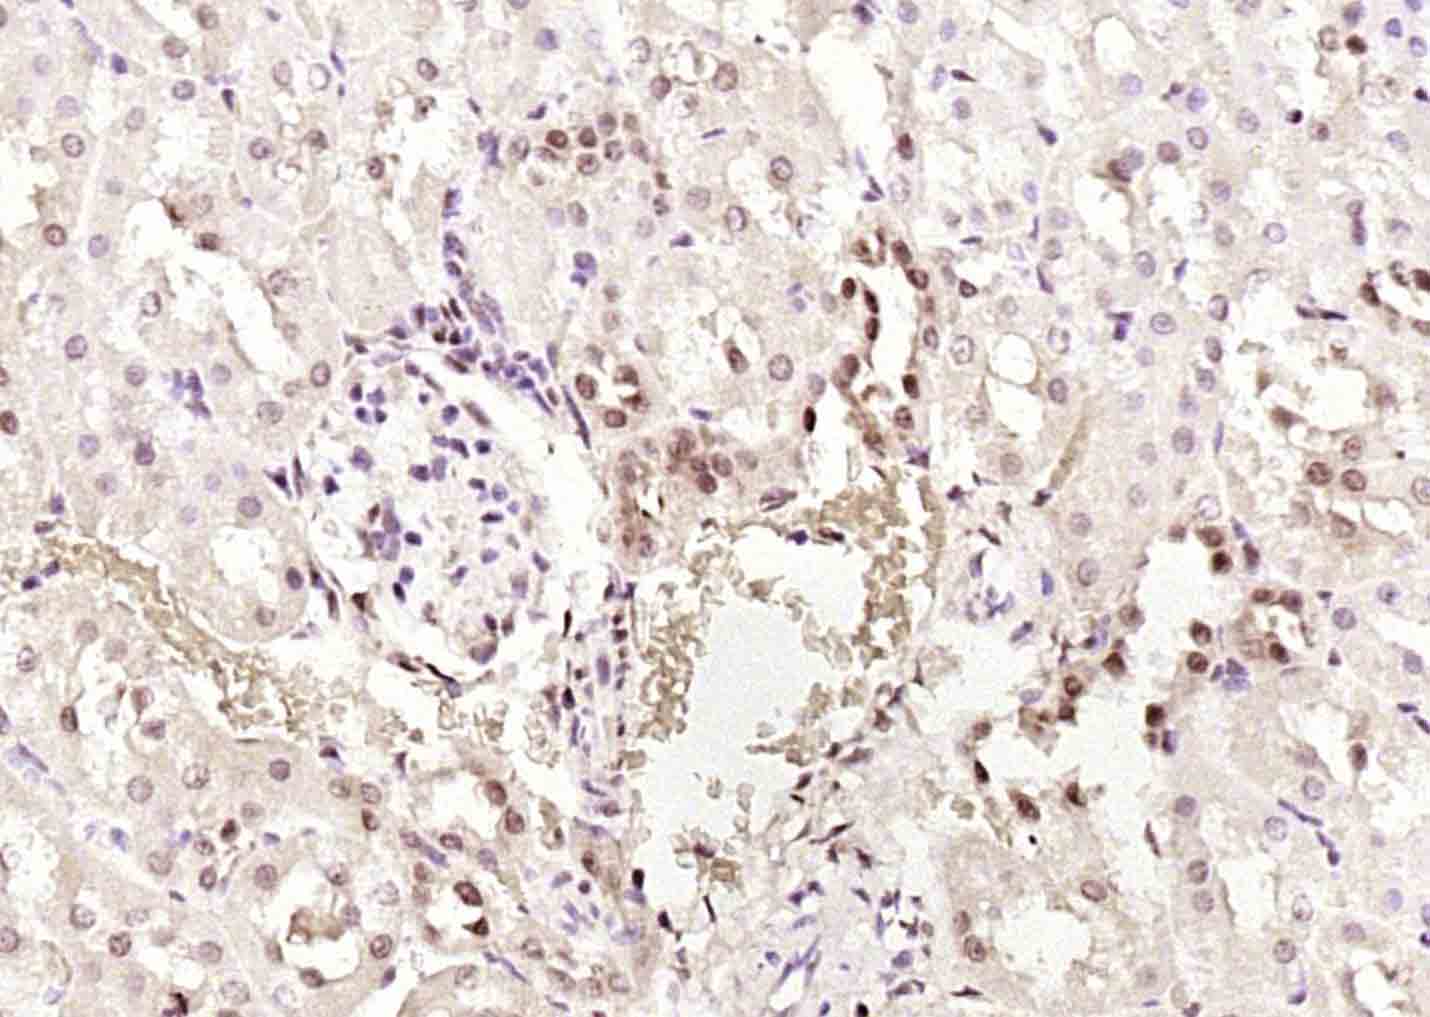

Paraformaldehyde-fixed, paraffin embedded (rat kidney); Antigen retrieval by boiling in sodium citrate buffer (pH6.0) for 15min; Block endogenous peroxidase by 3% hydrogen peroxide for 20 minutes; Blocking buffer (normal goat serum) at 37°C for 30min; Antibody incubation with (PTK5)) Polyclonal Antibody, Unconjugated (bs-6382R at 1:200 overnight at 4°C, followed by operating according to SP Kit(Rabbit) (sp-0023) instructionsand DAB staining.